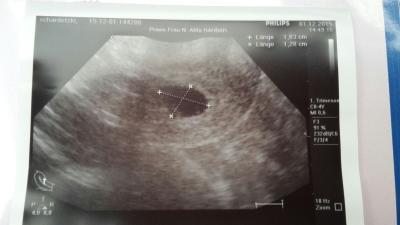

Hallo, ihr Lieben! Ich hatte am Dienstag (6+1) meine erste Untersuchung bei meiner Frauenärztin. Laut ihrer Aussage war nur eine Fruchthöhle und ein Dottersack zu sehen, was für den Zeitpunkt nicht außergewöhnlich sei. Leider kann ich auf dem US-Ausdruck aber nicht viel erkennen... Fruchthöhle - ja, aber Dottersack...? Könnt ihr einen erkennen? LG!

Links unten in dem dunklen Fleck lässt sich ein Schatten erkennen. Ich schätze das wird dann das baby sein. Herzlichen Glückwunsch.

Klaro sieht man da :) der Dottersack ist der kleine helle Kreis in der etwas schwarzen Blase. Das schwarz dargestellte ist die Fruchthöhle. Ich weiß nicht wie ich es anders sagen soll xD Also alles bestens, sah bei mir absolut identisch aus bei 6+1. Schöne Kugelzeit euch 2